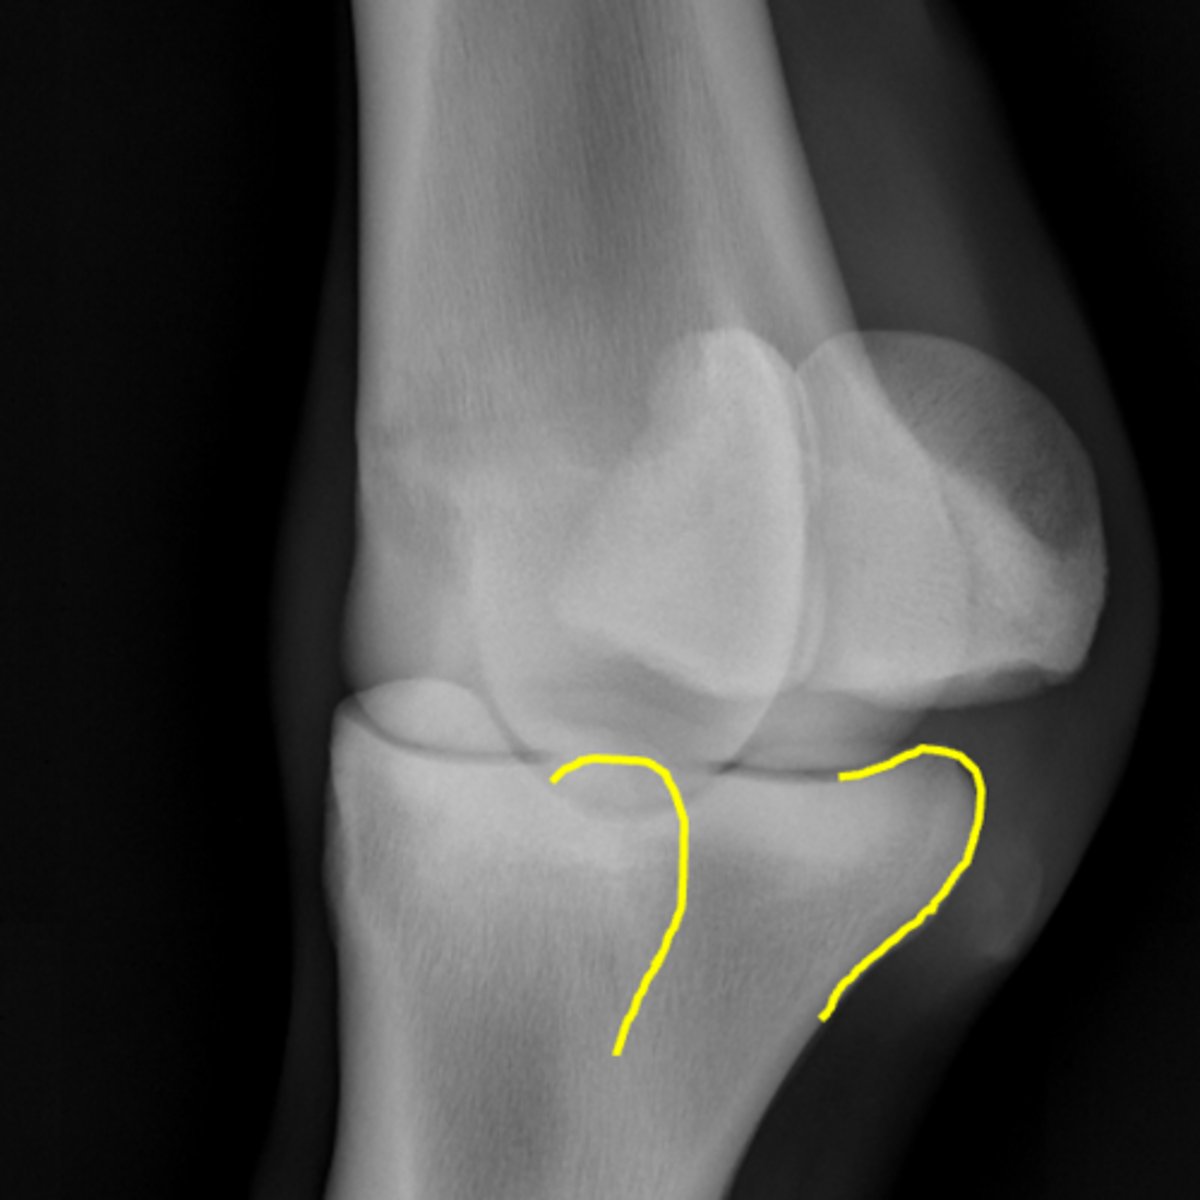

Fetlock joint, flexed LM

ID joint and view

Palmar process of P1